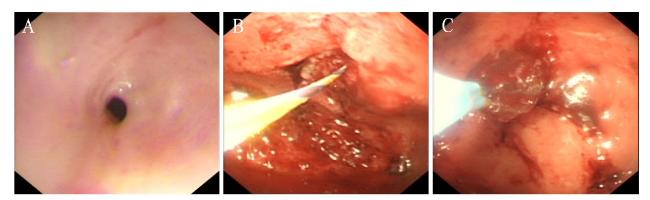

患者入院后于2021年8月24日行胃镜检查提示食管入口、食管中下段距门齿约30~40 cm处明显狭窄(图1A),予探条扩张后方能入镜至胃内,见胃窦变形,小弯侧大片溃疡形成,底覆白苔,周边黏膜充血水肿,幽门结构难以辨认(图1B),予球囊扩张(图1C),并放置鼻空肠管,术后第二天予肠内营养,但患者出现恶心、呕吐以及腹胀症状。2021年8月25日行上消化道碘剂造影显示食管上段、中下段狭窄,造影剂通过欠顺畅(图2);部分胃体、胃窦僵硬、狭窄并梗阻。心理科会诊提示患者有消极轻生念头,考虑为抑郁焦虑状态。经上述治疗后,患者肠内营养耐受情况欠佳,病情未见明显改善,梗阻仍然存在。经医务人员综合评估,确认该患者具有行PEG/J的适应证,无禁忌证。获得患方知情同意后,于2021年8月28日在气管插管全身麻醉下行PEG/J。患者取仰卧位,麻醉后经口插入胃镜,见食管仍狭窄,入镜至胃内,见胃腔变形,胃底较多胃液潴留,吸净后继续入镜至胃窦、幽门前区,见幽门仍狭窄,仔细辨认后送镜至十二指肠,见球部、降段黏膜光滑,退镜至胃体部,注气后于左上腹反复运用传统指压试验及透光试验寻找理想穿刺点,由于胃腔变形、胃移位,术者反复多次选点失败,后联合运用负压针吸试验,用含5 mL 生理盐水的注射器抽吸针筒保持负压,同时保证胃腔内充分注气,再次选定穿刺点后经腹部皮肤逐层缓慢穿刺至胃腔(图3A),最终定位于剑突下2 cm偏左约3 cm,消毒铺巾后,采用牵拉法完成胃造瘘术,并经胃造瘘管(管径6 mm)送入小肠管(管径3 mm)至空肠上段(图3B[5]。患者术中、术后生命体征平稳。于术后6 h开始向小肠管内注入少量营养液并逐量增加至正常管饲量,后逐渐过渡至日常食糜。经处理,患者病情及营养状况逐渐好转,于2021年9月25日出院。1个月后患者遵嘱返院复诊,监测体质量由住院期间最轻时39 kg增至47 kg,复查碘剂造影示食管上段狭窄较前减轻,中下段食管狭窄;胃窦部至幽门区明显狭窄伴梗阻,仅见少许造影剂通过幽门。医师与患方保持电话随访至撰稿日,得知患者呕吐次数逐渐减少至缓解,营养状况持续改善,造瘘管固定良好,造瘘口无红肿、渗液等(图3C)。

图3 一例上消化道严重腐蚀伤患者的PEG/J及腹部图片

注:A为负压针吸试验时注射器针头(箭头所示)刺入胃腔;B为经胃造瘘管送入小肠管至空肠上段;C为术后随访造瘘管、造瘘口情况良好。